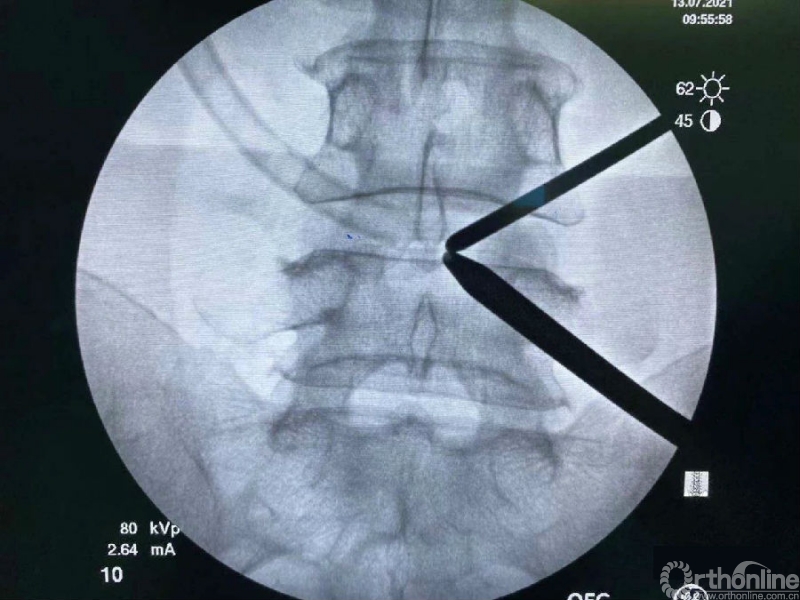

内镜监视下使用mark小磨钻进行第一定位,发现定位线过于偏内。

然后在内镜监视下于第一个孔的外侧进行第二次定位。